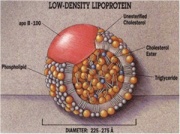

| 21:47, 12 בנובמבר 2012 | LDL1.jpg (קובץ) |  |

35 קילו־בייטים | Nachi | 1 | |

| 21:49, 12 בנובמבר 2012 | LDL2.jpg (קובץ) |  |

81 קילו־בייטים | Nachi | 1 | |

| 21:50, 12 בנובמבר 2012 | LDL3.jpg (קובץ) |  |

59 קילו־בייטים | Nachi | 1 | |

| 21:52, 12 בנובמבר 2012 | LDL4.jpg (קובץ) |  |

138 קילו־בייטים | Nachi | 1 | |